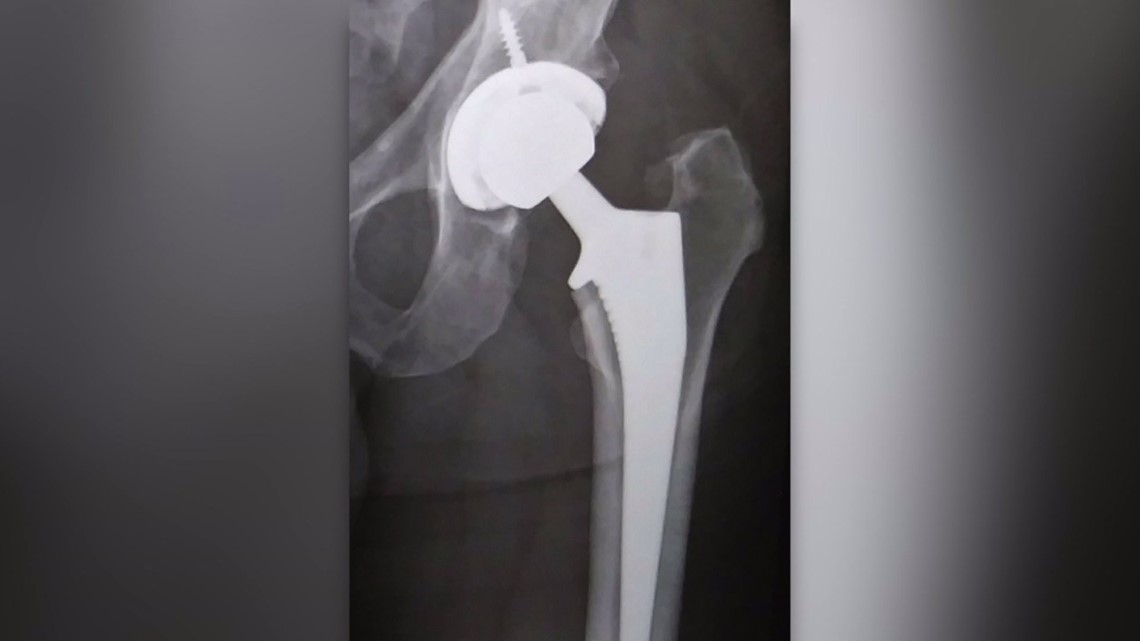

The latest trend in hip replacements CBC News